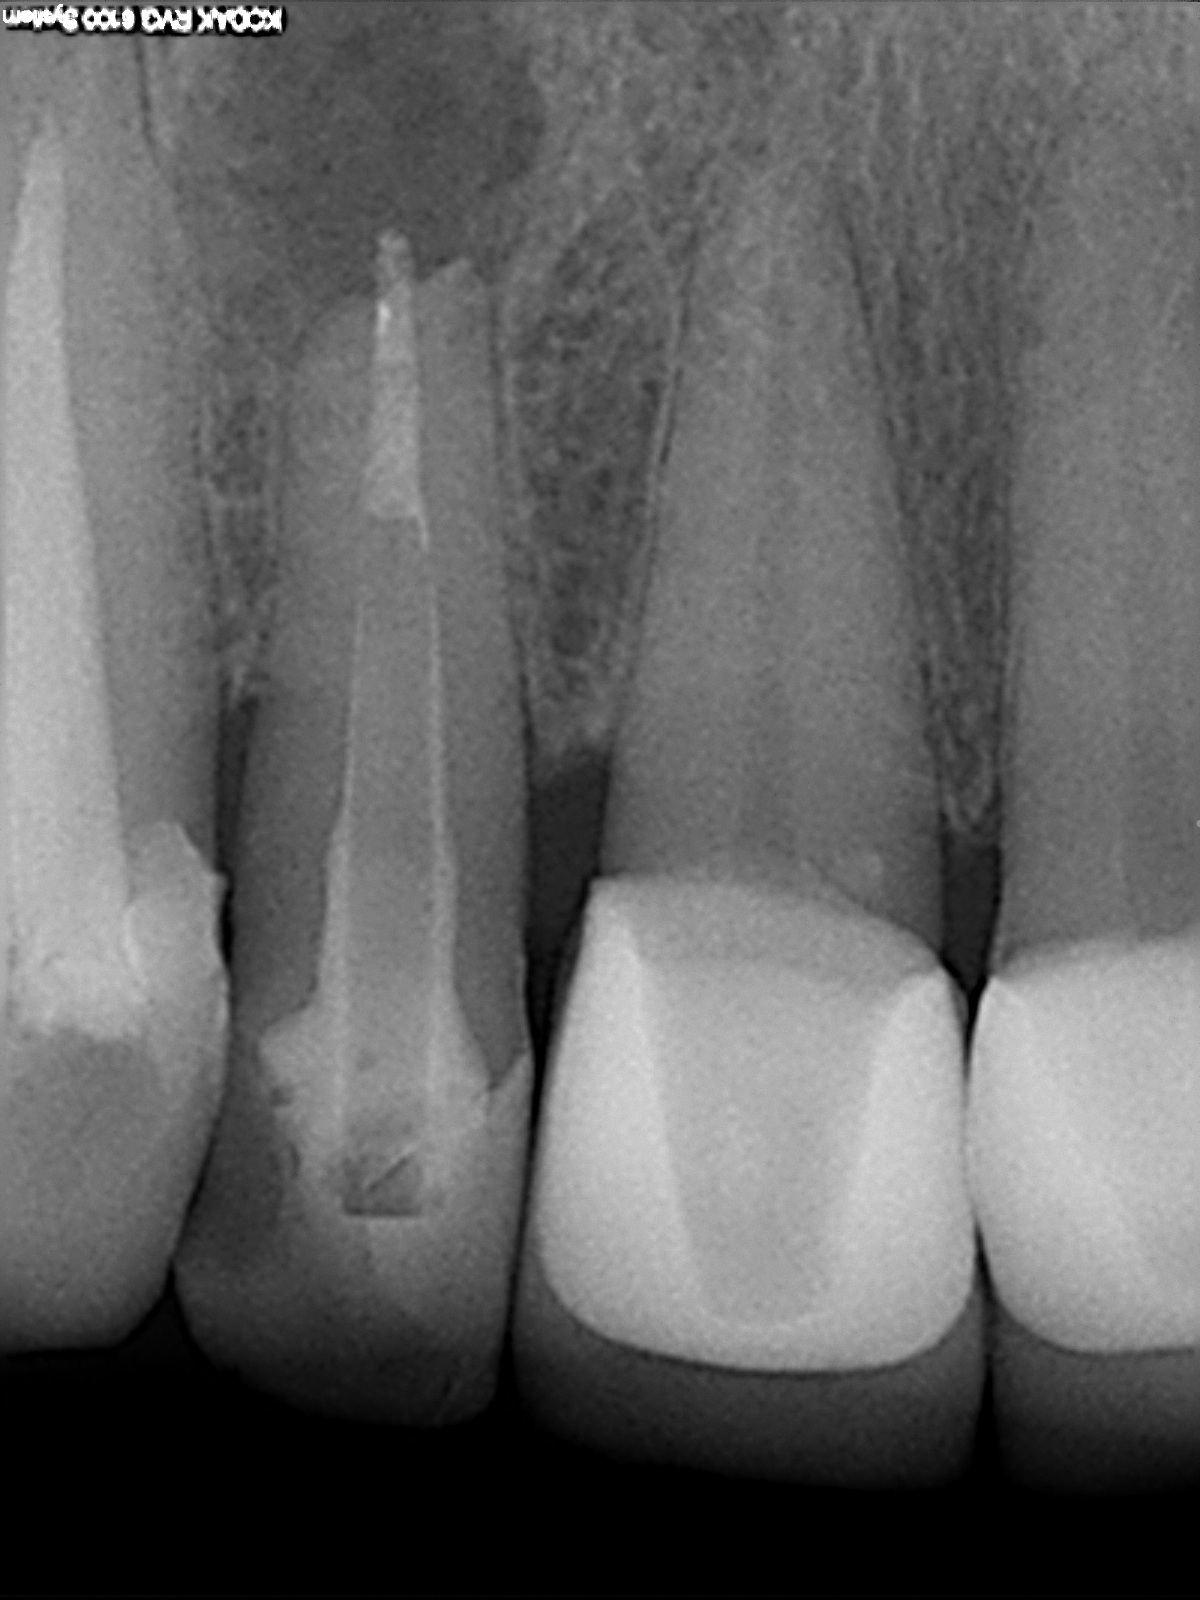

Z.n. Revision – dezente MTA Extrusion

1200 × 1600

WSR